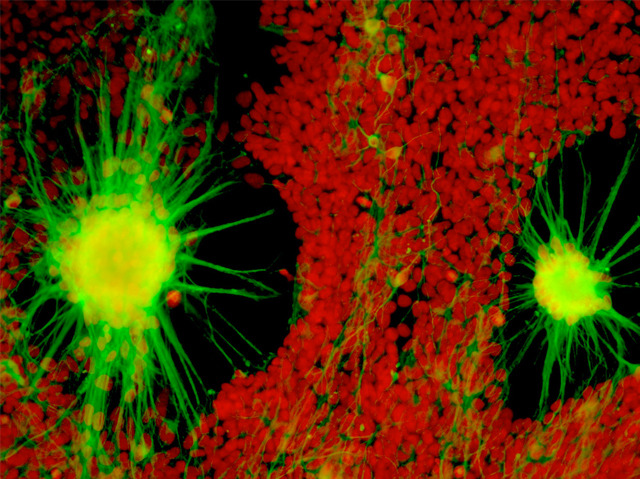

Autism impairs people’s ability to communicate with and relate to others. It’s a diverse condition, and its genetic causes have been difficult to pin down. Now, researchers are tackling the problem on a patient-by-patient basis. They reprogrammed cells from an autistic boy into induced pluripotent stem cells, then coaxed them to become neurons. Under a microscope, the neurons (pictured, green) had fewer branches and fired less than healthy controls. Suspecting a mutation in a gene called TRPC6, scientists treated the cells with a drug that boosts TRPC6 activity. As a result, the neurons fired like normal, suggesting that this mutation – which had not been linked to autism before – contributes to the boy’s condition. There are probably more mutations involved, but the study shows how stem cells might help identify categories of autism with different causes. In the long run, the approach could help diagnose and find treatments for individual patients.